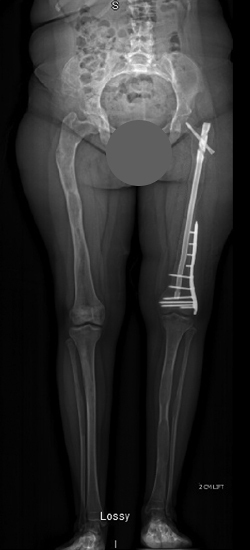

This X-ray shows how the hip & femur bone were deformed as a result of fibrous dysplasia.

Using the International Center for Limb Lengthening’s

Through a combination of fixator assisted nailing and plating techniques, the surgery to correct the bone deformity was performed in two stages, without the need for any